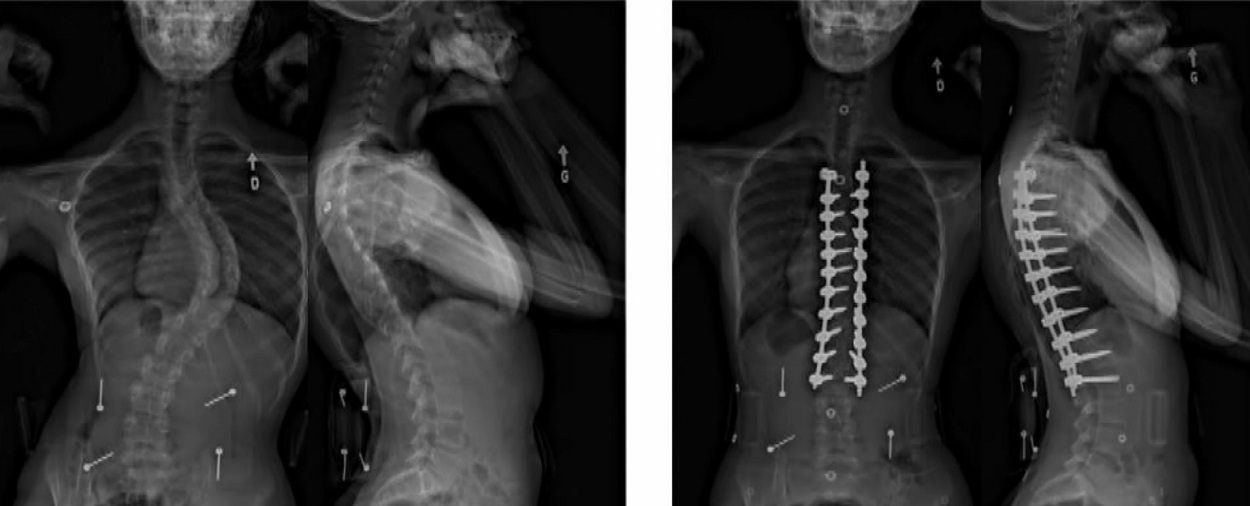

X-ray slide of scoliosis. Before operation (left) After operation (right) . Ste-Justine Hospital

“You’re working in close proximity to the spinal cord so there’s a small risk there,” Dr. Stefan Parent, the orthopedic surgeon who operated on Caroline explained. “She had over 50 degrees of deformity, we had tried bracing but that failed in her case.”